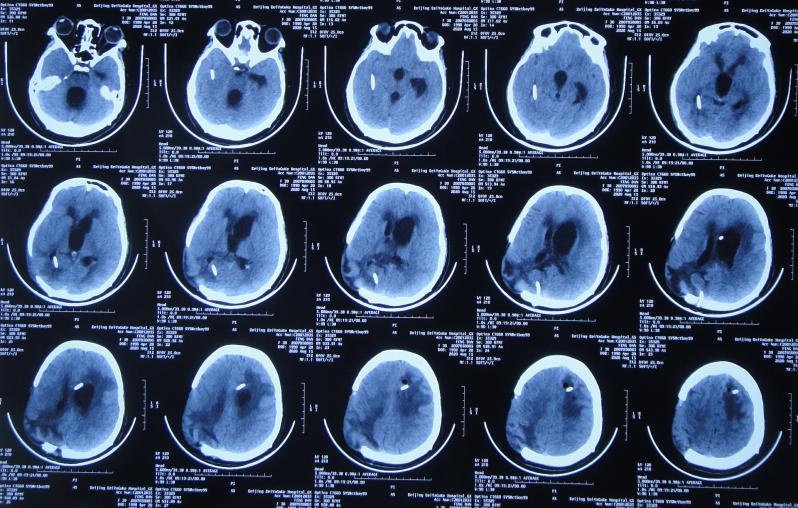

患者于2020年4月2日,在公司上班时突发头痛呕吐,急诊至陕西省西安市某二级医院,急诊查头颅CT检查示右顶叶脑出血破入脑室( 图-1 ),全脑血管造影示脑血管畸形(片子丢失);进行了开颅脑血管畸形切除术+去骨板减压术,术中留置引流外管;术后当天转入ICU继续治疗。

图-1: 2020年4月2日头颅CT